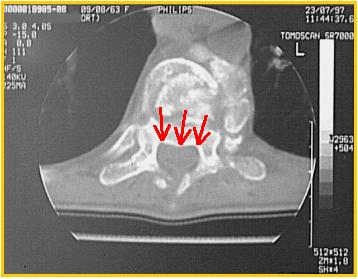

| Sezione TAC a livello della frattura somatica osservata alla RM. Nella sezione si può osservare bene l'integrità del muro posteriore e del canale vertebrale (frecce) che non viene invaso da frammenti di frattura. L'impronta osservata nella precedente immagine RM era da attribuire all'angolazione assunta dai segmenti vertebrali. |  |